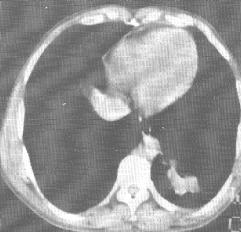

2、CT表現:

(1)氣管、主支氣管和葉支氣管腺瘤表現為管腔內結節狀腫塊,邊緣光滑。有壁外延伸時可並存管腔外腫塊。病變遠側常有阻塞性肺炎或肺不張。

(2)外圍型腺瘤表現為肺內軟組織密度結節,邊緣光滑。

支氣管腺瘤 X線表現 | 支氣管腺瘤 CT表現 | 支氣管腺瘤 CT表現 |